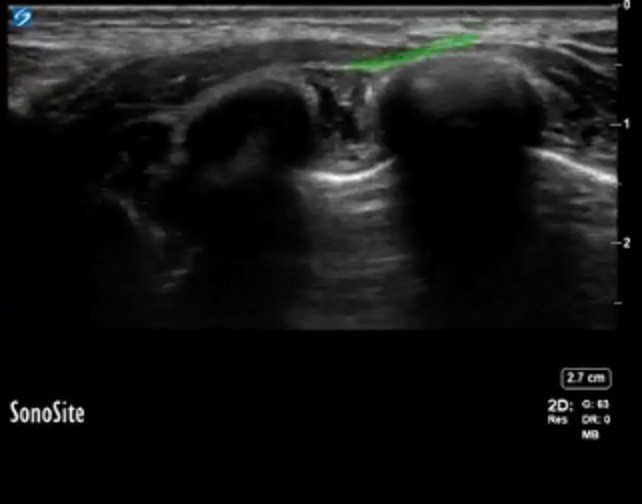

Serratus Injection Site Image

Highlighted Area: Injection Site